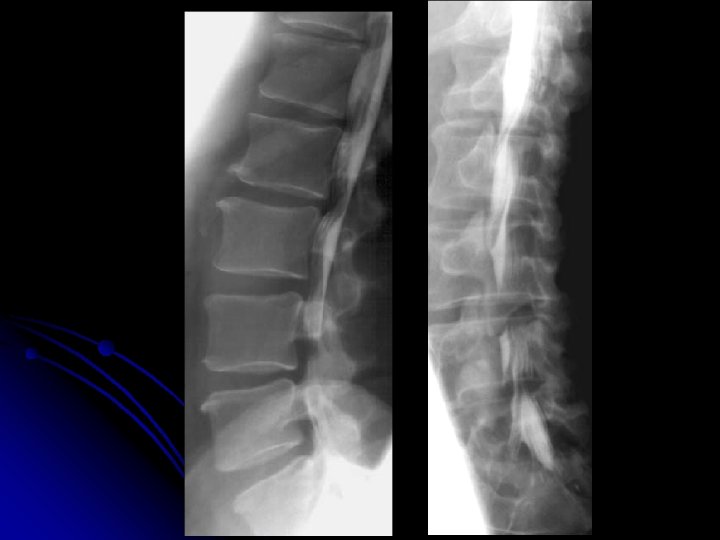

Rachis lombaire de profil

l Statique rachidienne l Morphologie et structure des corps vertébraux, l Hauteur des espaces inter-vertébraux l Morphologie des arcs postérieurs

l Autres incidences: l Cliché centré sur L 5 -S 1 l Obliques l Dynamiques